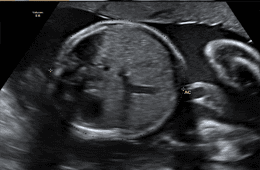

- Refah değerlendirmesi bebeğin pozisyonunu ve plasental pozisyonu içerir.

- Büyüme raporu, mevcut gebelikte bebeğin tahmini ağırlığını içerir.

- Amniyotik Sıvı indeksi ölçümü.

- Umbilikal arter Doppler ölçümü.

- Uterin Arter Doppler ölçümü.